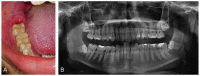

This work provides a narrative review covering evidence-based recommendations for pericoronitis management (Part A) and a systematic review of antibiotic prescribing for pericoronitis from January 2000 to May 2021 (Part B). Part A presents the most recent, clinically significant, and evidence-based guidance for pericoronitis diagnosis and proper treatment recommending the local therapy over antibiotic prescribing, which should be reserved for severe conditions. The systematic review includes publications analyzing sets of patients treated for pericoronitis and questionnaires that identified dentists' therapeutic approaches to pericoronitis. Questionnaires among dentists revealed that almost 75% of them prescribed antibiotics for pericoronitis, and pericoronitis was among the top 4 in the frequency of antibiotic use within the surveyed diagnoses and situations. Studies involving patients showed that antibiotics were prescribed to more than half of the patients with pericoronitis, and pericoronitis was among the top 2 in the frequency of antibiotic use within the monitored diagnoses and situations. The most prescribed antibiotics for pericoronitis were amoxicillin and metronidazole. The systematic review results show abundant and unnecessary use of antibiotics for pericoronitis and are in strong contrast to evidence-based recommendations summarized in the narrative review. Adherence of dental professionals to the recommendations presented in this work can help rapidly reduce the duration of pericoronitis, prevent its complications, and reduce the use of antibiotics and thus reduce its impact on patients' quality of life, healthcare costs, and antimicrobial resistance development.